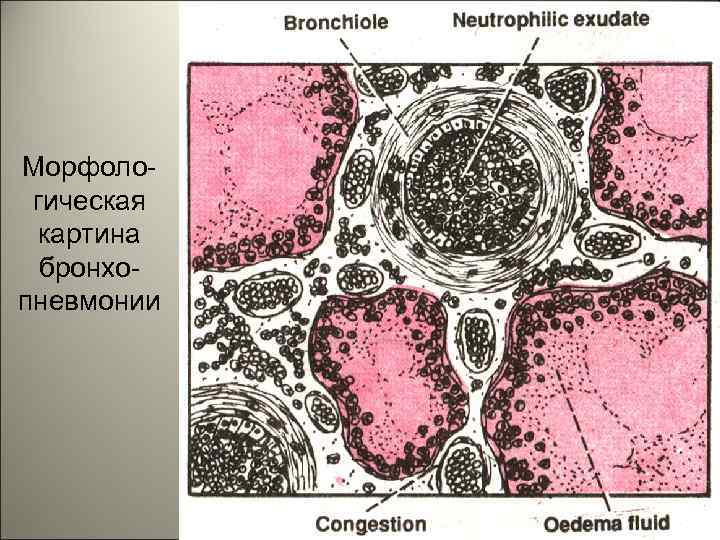

• Патанатомия. Очаги воспаления при бронхопневмонии обычно возникают в задних и задненижних сегментах легких, при этом развивается: I. Серозное воспаление вокруг бронхов (бронхит). II. В альвеолах экссудат с примесью слизи, много нейтрофилов, макрофагов, эритроцитов, небольшое количество фибрина. 66

• Экссудат по легким распределяется неравномерно, в одних альвеолах его много, в других – мало. В межальвеолярных перегородках – клеточный инфильтрат. Рентгенологически – очаговые затемнения, усиление легочного рисунка. Затемнение часто связано с бронхом. Характерна мозаичность поражения. 67

Морфологическая картина бронхопневмонии 69